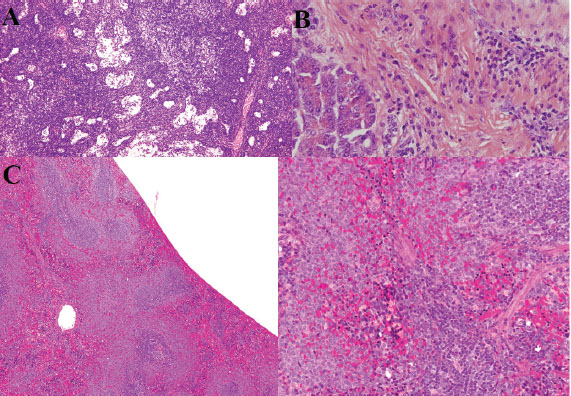

Histopathological findings

Lungs

Severe pulmonary edema, hyaline membrane formation, and intra-alveolar neutrophilic infiltration were noted. Intravascular fibrin thrombi and ectatic alveoli with focal atelectasis were also observed. Occasional megakaryocytes were observed within pulmonary capillaries, along with hemosiderosis and mild anthracosis (Fig. 4A,B). These pulmonary changes are consistent with ALI and DAD.

Mesenteric lymph nodes

Histological examination revealed marked architectural disruption with focal eosinophilic necrosis, extensive karyorrhexis, and karyolysis. A notable increase in reactive lymphocytes and plasmacytoid monocytes was observed. Numerous histiocytes were also observed, indicating intense immune activation. The changes reflect severe lymphoid necrosis and immune activation.

Spleen

The spleen exhibited pronounced white pulp atrophy and lymphocyte depletion. Extensive necrosis and vasculitis with arterial thrombosis were observed. Additional findings included congestion, hemorrhage, infarction, acute neutrophilic splenitis, and necrotizing granulomas. Hemophagocytosis was noted along, with the absence of distinct lymphoid follicles (Fig. 5C). These changes are consistent with severe splenic lymphoid depletion and vasculitis.

Fig. 5. Histopathology of lymphoid tissues, pancreas, and spleen. (A) Extensive necrosis, vascular thrombosis, cellular debris, lymphoid follicle depletion, and polymorphonuclear neutrophil infiltration. (B) Areas of inflammatory infiltration in the pancreas (hematoxylin and eosin staining, 400X). (C) Depletion of lymphoid follicles in the spleen and reduction of lymphocytes (hematoxylin and eosin staining, 300 dpi).